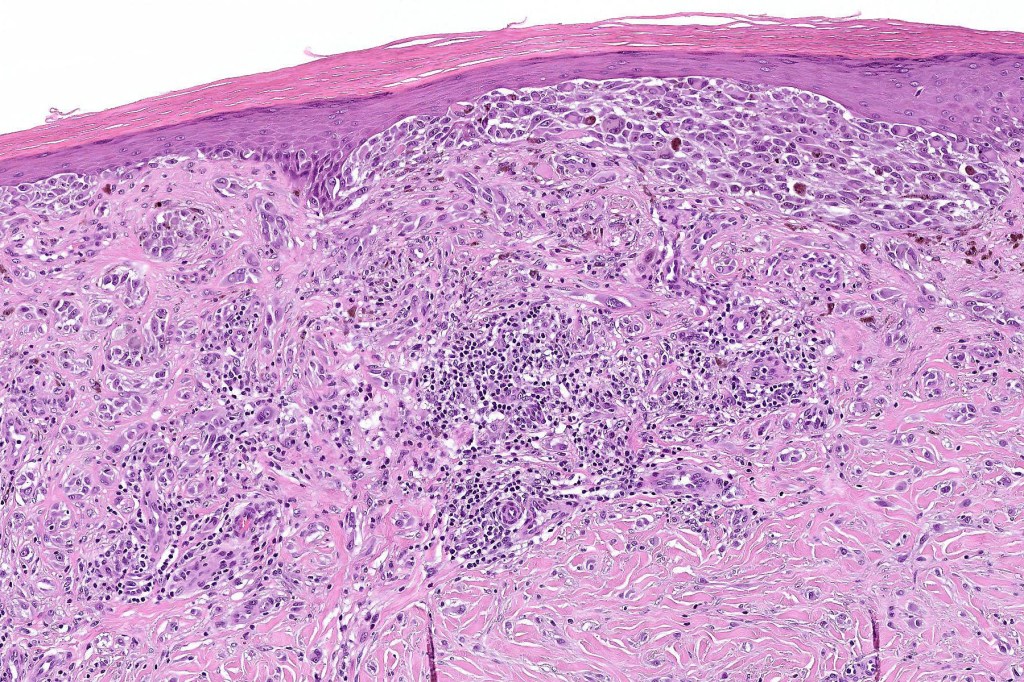

Histological features

•>5-10 mm

•Involve deep dermis or subcutis

•Asymmetrical, poorly circumscribed

•May show effacement/consumption of epidermis or ulceration

•Peripheral Pagetoid spread

•Large nodules which often show impaired maturation